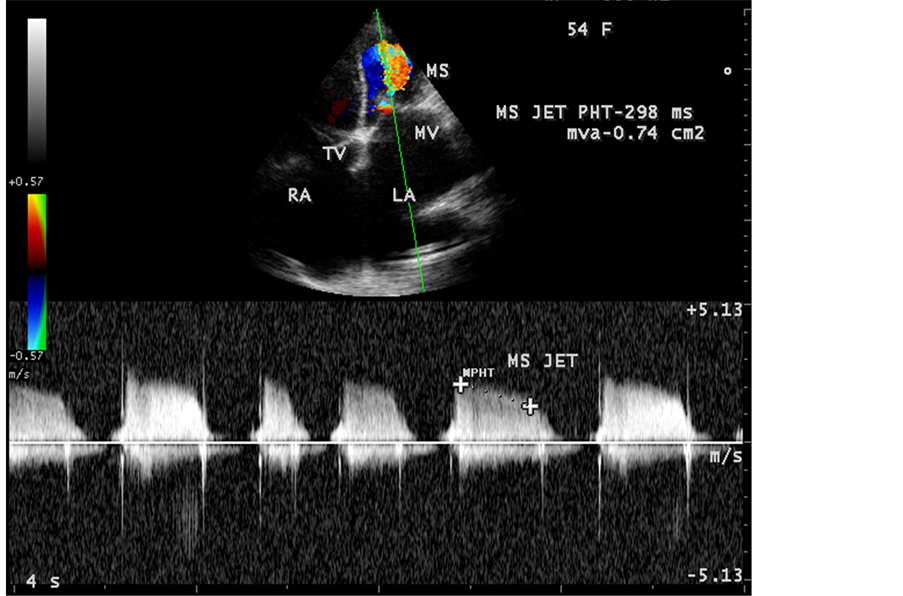

Figure 59. Showing the severe rheumatic mitral stenosis jet in a 54-year-old female.